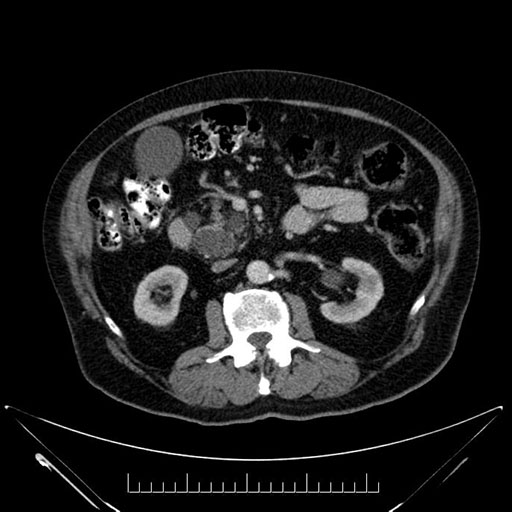

Imaging Analysis

Look through the patient's CT scan to identify any areas of concern for the necessary procedure.

Based on your CT findings, which issue(s) would give reason for "planned slowing down moment(s)" in this case?